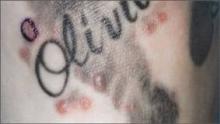

Tattoo ink contaminated with Mycobacterium chelonae caused skin infections in 19 people in one New York county last year, underscoring the need for regulatory oversight of tattooing and the inks used in tattooing to ensure public safety.

In January, public health officers received a report of a male patient with a persistent granulomatous rash on a recently tattooed area of his arm, wrote Dr. Kennedy, deputy director of the Monroe County public health department, and his colleagues. The patient had received a number of tattoos in his town of Rochester, and had never experienced any reaction. His primary care physician had unsuccessfully treated him with glucocorticoids, so he was referred to a dermatologist. Histopathology showed infection with M. chelonae.

Health department investigators found similar reactions in patients who received tattoos from the same artist at the parlor. During May-December 2011, the artist had been using a new brand of premixed, hand-blended, diluted gray ink as a wash to produce shadow effects. The product contained pigment, distilled water, witch hazel, and glycerin. It was packaged in 20%, 60%, and 90% dilutions.

The investigation identified 19 subjects who developed a similar erythematous rash after receiving tattoos from the same artist at the same location. Clinical results were available for 17. Twelve showed sparse lymphohistiocytic infiltrates in the upper dermis. Granulomas were present in five and acid-fast bacteria in two of the patients. DNA sequencing identified M. chelonae as the causative agent. The organism was also found in an unopened bottle of the 30% dilution ink.